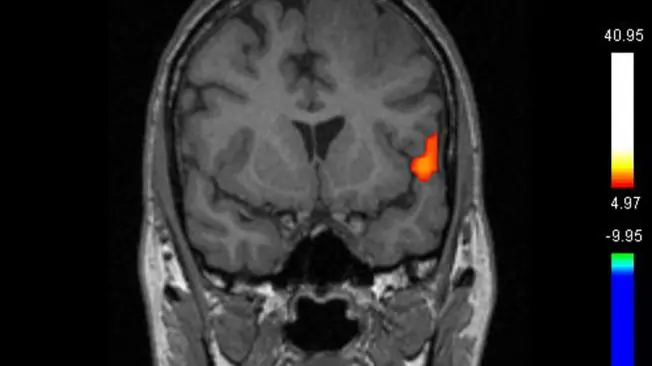

Elaboraron el primer mapa 3D completo del cerebro humano

Muestra la actividad de los genes en todo el órgano. Serviría para conocer, en un futuro, los factores que causan los trastornos neurológicos y psiquiátricos.

Un grupo de científicos de Estados Unidos creó un mapa del cerebro de una persona adulta, el primero de este tipo en el mundo, que muestra la actividad de los genes en todo el órgano, publicó el diario Clarín.

El mapa fue creado a partir de análisis genéticos de cerca de 900 partes específicas de dos cerebros “clínicamente comunes y corrientes”, donados por dos hombres (uno de 24 años y el otro de 39), y de medio cerebro de un tercer individuo.

A partir de las más de 100 millones de mediciones que se realizaron en los cerebros analizados, los científicos descubrieron que el 84 por ciento de los genes son activados en alguna parte de este órgano. La actividad genética en regiones contiguas de la corteza, esa gran superficie rugosa del cerebro, era similar pero diferente de la vista en las partes inferiores, como el bulbo raquídeo.

Según indicó Clarín, un análisis más detallado de la corteza permitió ver patrones en la actividad genética que se correspondían con regiones con papeles específicos del cerebro, como las funciones sensorial y de movimiento. El mapa no mostró ninguna división importante de la actividad genética en los costados derecho e izquierdo del cerebro, lo que sugiere que la habilidad o destreza que maneja un hemisferio, como el lenguaje, proviene de diferencias más sutiles que las que pudo detectar el estudio.